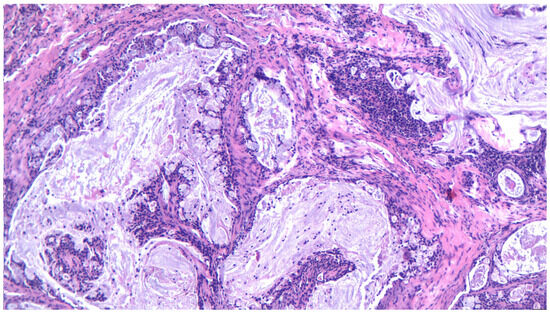

3.14. Mucoepidermoid Carcinoma